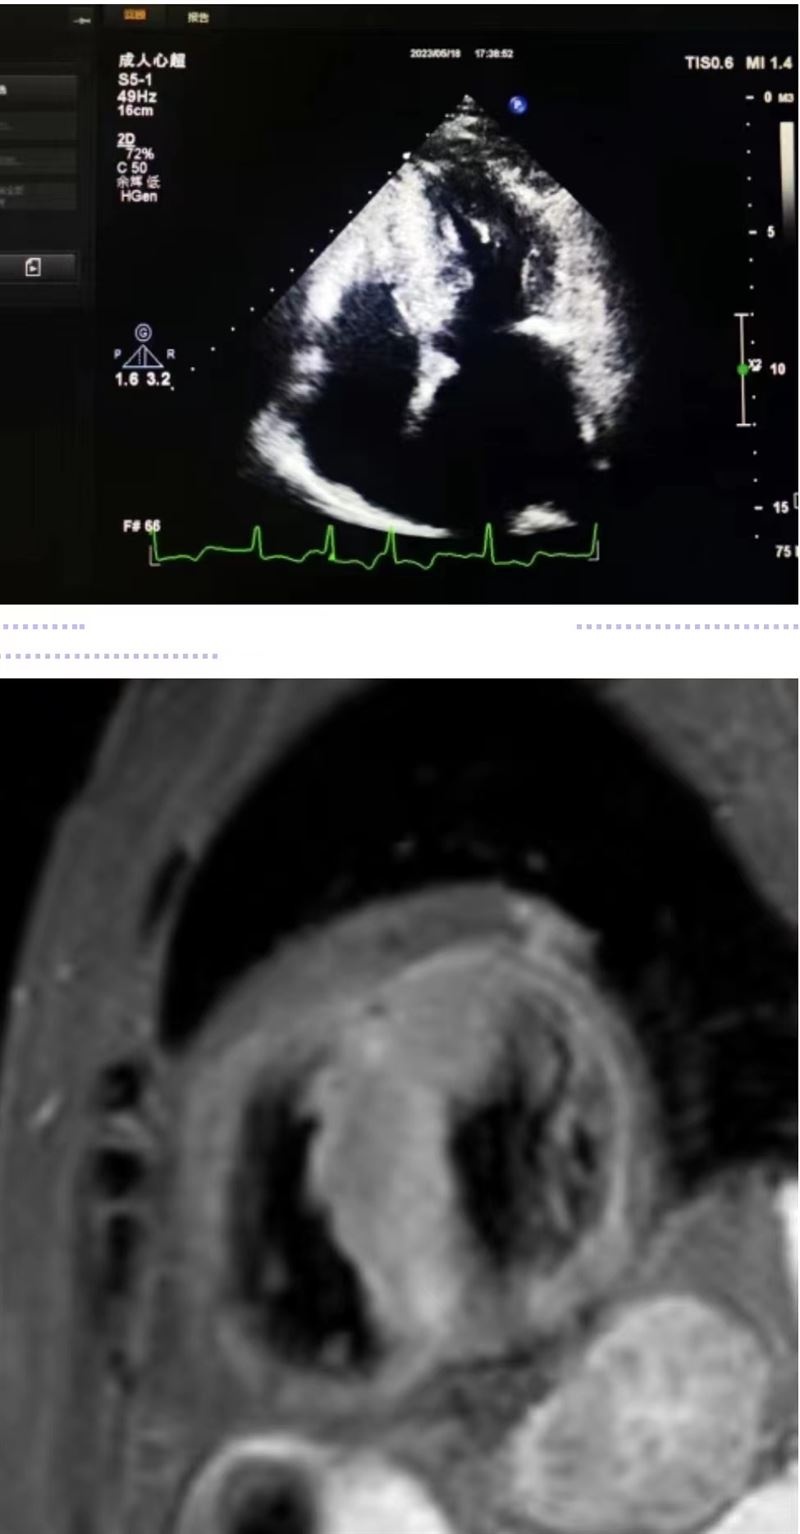

超声科王英莉主任及心血管组贾贝主治医师、陈辉主管护师及牛丹青护师为该患者行药物负荷超声心动图。监护仪、急救车到位,常规经胸超声心动图提示室间隔增厚,左室流出道血流速度略增快,左心腔超声造影,可清晰显示室壁显著增厚,符合肥厚型心肌病表现,随后又进行了多巴酚丁胺负荷超声心动图,静息状态下显示左室流出道血流速度V:207cm/s,PG:17mmHg;3分钟后心率达75次/分,左室流出道血流速度V:218cm/s,PG:19mmHg;6分钟后心率达94次/分,左室流出道血流速度V:386cm/s,PG:60mmHg;9分钟后达到目标心率,左室流出道血流速度V:649cm/s,PG:169mmHg,停止用药,药物负荷试验阳性,检查过程中患者无不适症状,最终诊断为隐匿性肥厚型梗阻性心肌病。